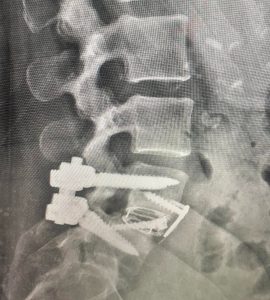

At Texas NeuroSpine Surgery, our goal is to always find the least invasive approaches for the best surgical outcome. However, some cases require more extensive approaches, as in this case of an L4-5 deformity in a patient with rheumatoid arthritis and years of debilitating low back pain. A “front-back” or “anterior-posterior” surgery was needed to correct her deformity and stabilize her spine.

A few weeks after surgery, the patient was off pain medication and resuming work and normal activities. Although not every patient recovers as quickly, this type of extensive surgery offers a solution to many patients who have failed less invasive treatment.